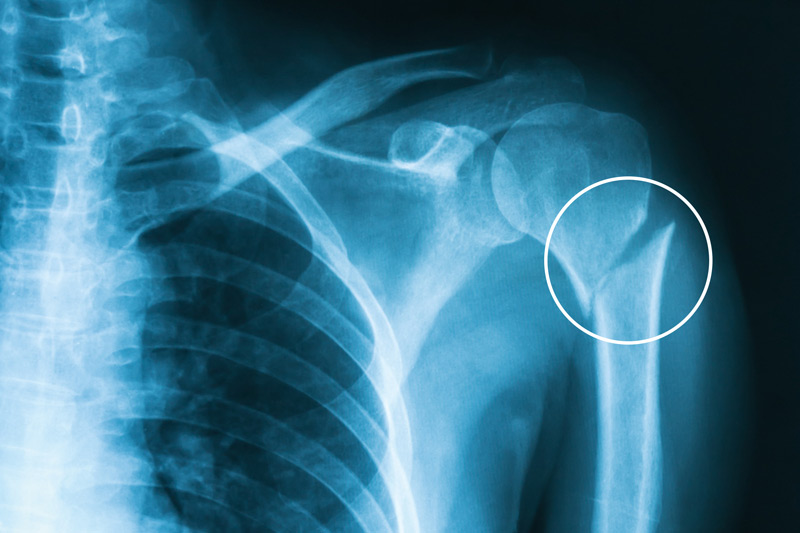

Diagnose this injury. Provide Moi, signs and symptomsand management

humerus fracture

moi - fall on outstrectched arm / direct blow (often with disclocation)

signs and symptoms - pain , redness and discolouration, sweling, tenderness, inability to move arm

management - splint and sling, pain relief, refer to medical professional